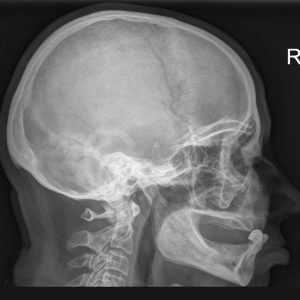

При рентгенологическом исследовании височной кости в клинической практике чаще всего используются рентгенограммы, выполненные в проекциях Шюллера, Майера и Стенверса (осевая, косая и поперечная проекции). Каждая из них позволяет получить информацию о состоянии определенного отдела височной кости. Вопрос о необходимости использования того или иного положения больного решается врачом самостоятельно с учетом клинической картины болезни.

Так, если нужно подтвердить или исключить мастоидит у больного с острым гнойным средним отитом, применяется обзорная рентгенограмма в проекции Шюллера, потому что именно эта проекция позволяет наиболее четко выявить клеточную структуру сосцевидного отростка и других отделов височной кости, а также установить там наличие патологических изменений. В тех случаях, когда у больного хроническим гнойным средним отитом нужно оценить выраженность патологических изменений в барабанной полости, сосцевидной пещере и входе в нее, а также в прилежащих отделах височной кости, используется рентгенография в косой проекции по Майеру.

При обследовании больного с подозрением на невриному VIII пары черепных нервов или травматический перелом пирамиды височной кости назначается рентгенограмма в поперечной проекции по Стен-версу, позволяющая получить удовлетворительное изображение внутреннего слухового прохода. Приведенные примеры иллюстрируют лишь малую часть различных клинических ситуаций, когда ценную информацию можно получить, используя рентгенографию височных костей.

Приступая к рассмотрению некоторых технических деталей выполнения рентгенограмм при болезнях уха, следует отметить, что при исследовании в любой проекции необходимо получить рентгенограммы обеих височных костей. Это обусловлено, в частности, тем, что возможны анатомические варианты строения этих костей, которые могут быть учтены только при сравнивании рентгенограмм здорового и больного уха или правого и левого уха, когда имеется двустороннее поражение.